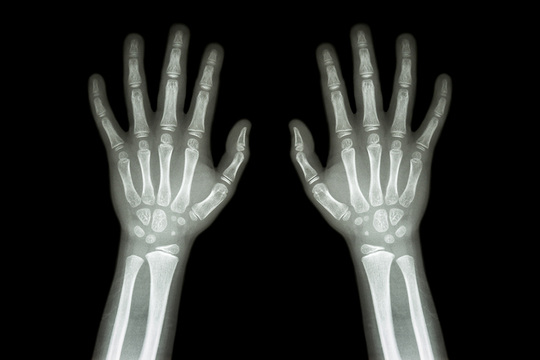

お子さんの矯正の場合、上記の検査に加えて「手根骨(しゅこんこつ)のレントゲン撮影」を行います。手根骨とは、手首から指先までのいわゆる「手の骨」のことです。

「歯の治療なのに、なぜ手の骨の写真が必要なの?」と不思議に思う方もいらっしゃるかもしれません。実はこの手根骨を詳しく調べると、骨年齢、つまり骨の年齢を割り出せるのです。

骨年齢は、さまざまな要因から暦年齢(実際の年齢)とズレが生じる場合があります。そのため骨年齢と暦年齢を比べれば、体の成長の度合いを導き出すことが可能です。

お子さんの成長の状況は、一人ひとり異なります。ある時急に背が伸びることもあれば、しばらく停滞期間が訪れることも珍しくありません。そして、体の成長に合わせて下あごの骨も変化しますので、その子の成長具合の把握が重要です。私たちは手根骨のレントゲン検査の結果も踏まえ、一人ひとりにとって、より適切な治療計画を検討します。